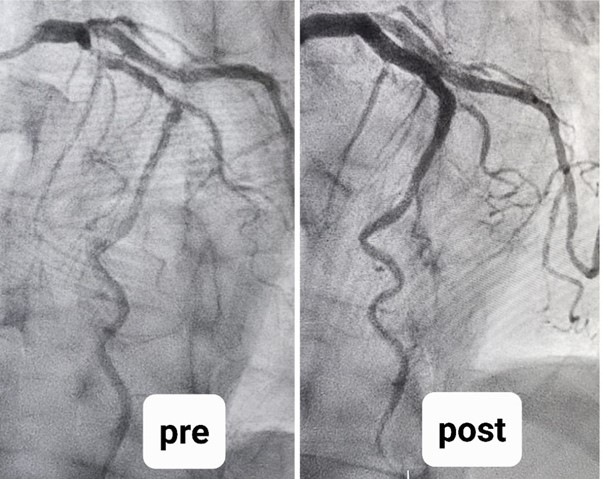

1) Coronary physiology is the use of a wire with sensors down the blockage to measure the significance of it to decide if an intervention now can reduce the need of an urgent unanticipated intervention downstream. Such data has been well validated and replaces the visual estimations on angiograms.

2) Coronary imaging is the use of a catheter-based device down the blockage to analyze the characteristics of the plaque to determine the type of preparatory devices needed to modify it before stenting. It also allows for accurate stent diameter and length measurements to optimize the longevity of the stent.